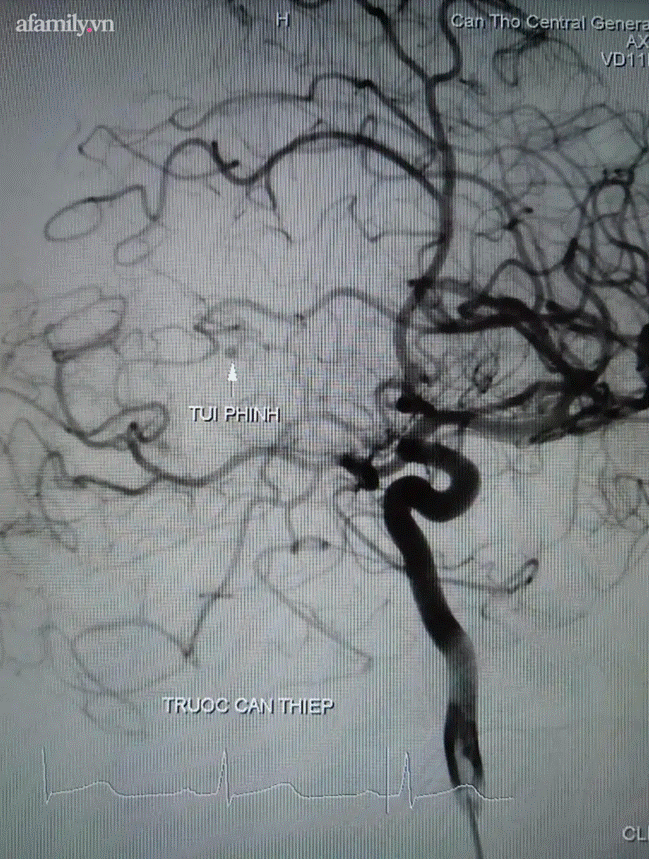

Hình ảnh túi phình bệnh nhân T. sau can thiệp.

Tình trạng sau khi phẫu thuật vẫn rất nặng, bệnh nhân tiếp tục được theo dõi và hồi sức tích cực tại khoa Gây mê hồi sức. Sau 24 ngày điều trị tích cực bệnh nhân tiếp xúc được, sinh tồn ổn định, tự thở và vẫn đang tiếp tục được điều trị phục hồi.